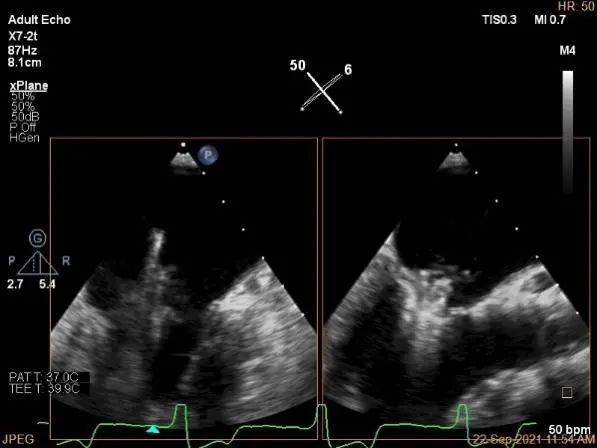

房间隔穿刺点选择

穿刺高度:4.3cm

过大鞘

出夹子,做trajactory

调rotate

夹子进左室

瓣叶捕获后,前叶抓捕长度9.1mm,后叶抓捕长度7.8mm

外侧残余少量分流

第一个夹子外侧残余小脱垂

残余分流主要来源于残余脱垂区域

评估瓣口条件,平均跨瓣压差:2mmHg,决定在第一个夹子外侧下第二个夹子